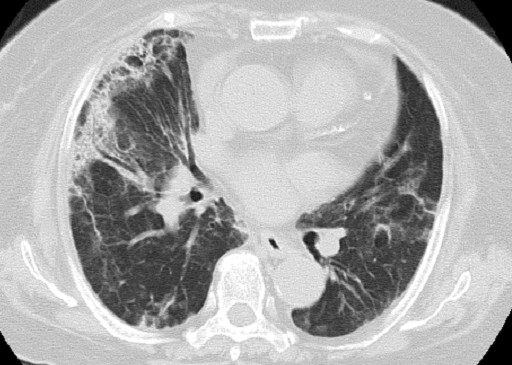

A 74-year-old woman was referred to our hospital with a 23x19 mm pancreatic body tumor with dilatation of pancreatic duct which was detected incidentally and was diagnosed with pancreatic cancer. It was clinically staged as T3N0 Stage II (UICC) and a distal pancreatectomy was then planned. However, the resection was discontinued due to peritoneal dissemination, and only a biopsy of the tumor was performed. The postoperative course was uneventful, but multiple liver metastases were found in a follow-up CT scan. Laboratory data showed the following levels: white blood cell count 10,200 mm-3 (WBC; reference range: 4,000-9,000 mm-3), C-reactive protein 1.07 mg/dL (CRP; reference range: 0-0.5 mg/dL), aspartate aminotransferase 60 IU/L (AST; reference range: 0-35 IU/L), alanine aminotransferase 59 IU/L (ALT; reference range: 0-40 IU/L), lactate dehydrogenase 259 U/L (LDH; reference range: 119-229 U/L), blood urea nitrogen 9 mg/dL (BUN; reference range: 8-20 mg/dL), and creatinine 0.66 mg/dL (reference range: 0.6-1.2 mg/dL). Soon after the CT scan, she began chemotherapy with gemcitabine 1,000 mg/m2 on days 1, 8, and 15 every 28 days. After her fourth course of the chemotherapy, she developed shortness of breath, and was dyspneic at rest. There was no finding of heart failure or evidence of a pulmonary embolism. A chest CT showed bilateral diffuse ground-glass opacities in both lungs (Figure 1). The radiological features seemed compatible with acute interstitial pneumonitis. An echocardiogram was normal. Laboratory data showed WBC 10,500 mm-3, CRP 9.46 mg/dL, AST 22 IU/L, ALT 15 IU/L, LDH 357 U/L, BUN 14 mg/dL, creatinine 0.54 mg/dL, and CA 19-9 348,440 U/mL (reference range: 0-37 U/mL). There was no elevation of antibody titers of Mycoplasma, Legionella pneumophilia, and Chlamydia psittaci. Antibiotic treatment was initiated with ciprofloxacin on admission; however, her respiratory status rapidly deteriorated. Suspecting gemcitabine-induced pneumonitis, the gemcitabine was discontinued and the patient was treated with methylprednisolone (500 mg/day) for 3 days. A lung biopsy was planned but the patient’s respiratory condition improved after steroid therapy, so the procedure was not performed. On the 21st day of hospitalization, a chest CT showed the disappearance of the diffuse ground-glass opacities in both lungs (Figure 2). The steroids were gradually tapered off. Due to concerns of gemcitabine-induced pulmonary pneumonitis, the chemotherapy was changed to S 1 combination monotherapy.

Figure 2. Chest CT showing the disappearance of ground-glass opacity in both lungs after discontinuation of the drug, administration of corticosteroids and pulmonary support. |